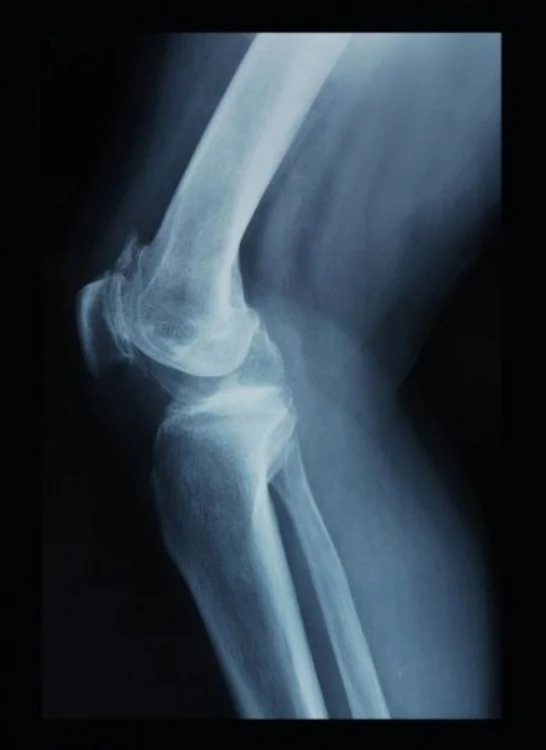

Primul ajutor în caz de fracturi

În majoritatea cazurilor, în fracturile de orice natură (de gleznă, coaste, femur, braţe sau de coloană), terapia începe cu ameliorarea durerii.